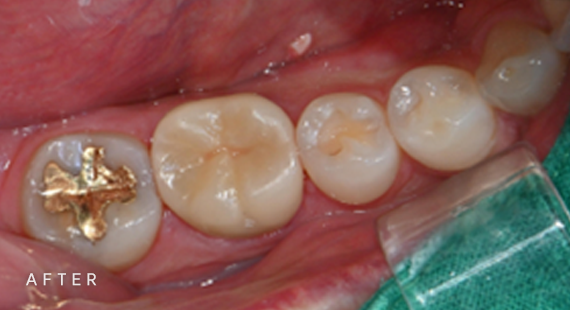

충치치료